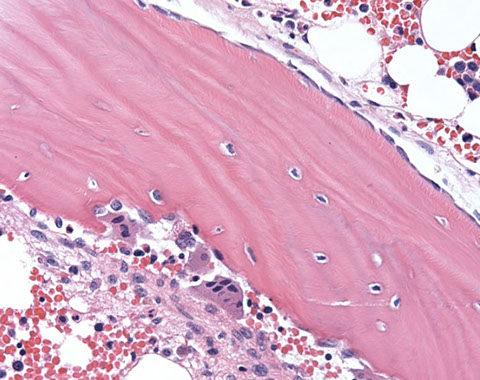

sites of hematopoiesis [1]

Normal trabecular bone